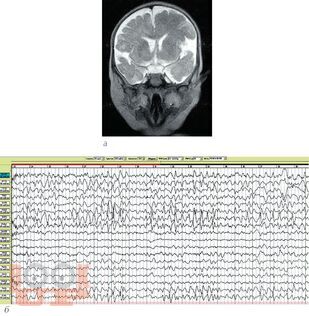

В учебном пособии рассматривается проблема диагностики и лечения резистентных форм эпилепсии у детей. Анализ материала основан на собственном опыте работы и данных литературы. В пособие включены редкие формы резистентных эпилептических энцефалопатий у детей. Особое внимание уделено нейрохирургическим методам лечения.